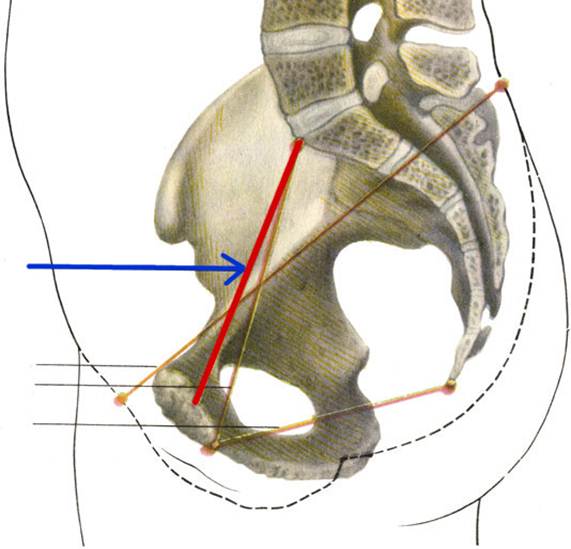

S: Стрелка указывает на Conjugata vera

S: Стрелка указывает на Conjugata diagonalis

S: Стрелка указывает на lig. Sacrospinale

S: Стрелка указывает на лобковый симфиз (русский язык).

S: Стрелка указывает на art. sacroiliaca (латинский язык).

S: Стрелка указывает на foramen ishiadicum majus

S: Стрелка указывает на foramen ishiadicum minus

S: Стрелка указывает на lig. Sacroiliaca posteriora

S: Стрелка указывает на lig. Sacrococcygeum anterius

S: Стрелка указывает на membrana obturatoria (латинский язык).